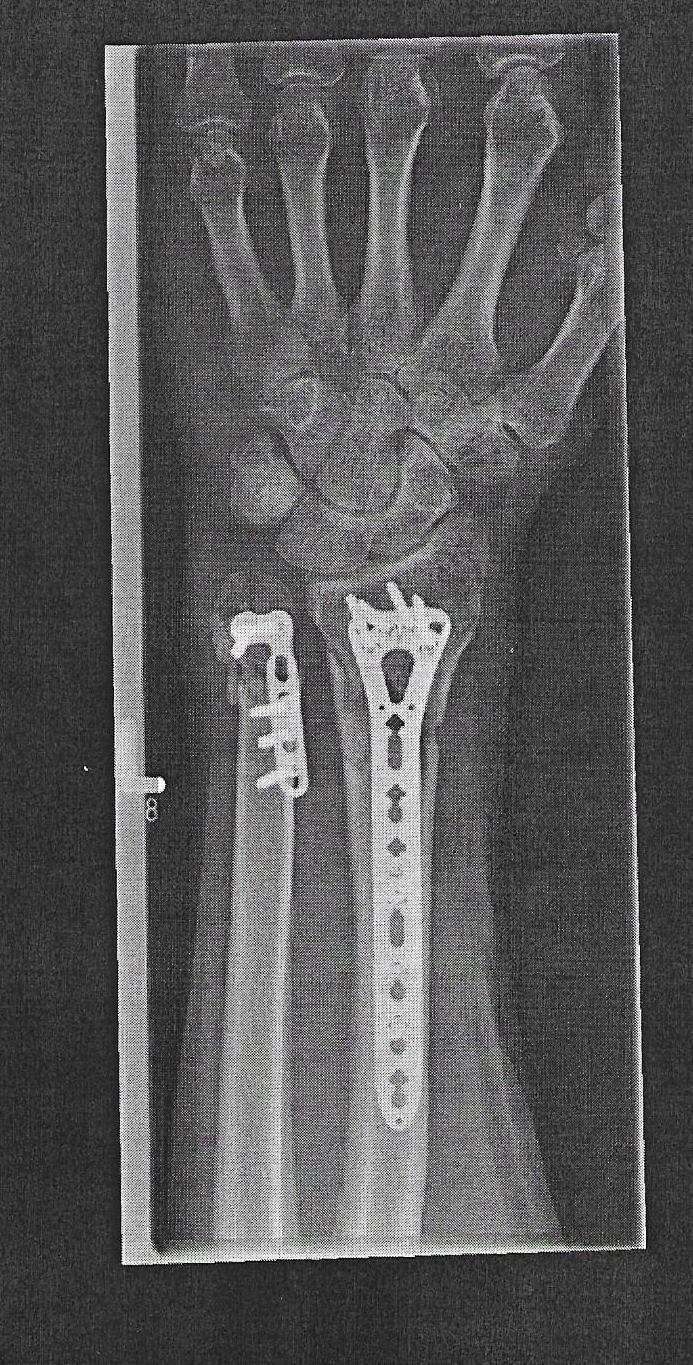

Nein, ist wirklich vergessen, dass vielleicht zu viel Gewebe zugewachsen ist, war auch 2 Jahre nach der Installation. Außerdem machen sie nicht "automatisch" ein Foto nach der OP.vergessene Schraube? die sieht man doch auf jedem billigen Rötgenbild..

Die kann ja nur absichtlich drin noch geduldet gewesen sein?

Dann haben Sie die anderen Bilder noch nicht gesehen diese sind auch hier in der Topikdas sieht ja echt überl ausSchnelle und Beste Genesung wünsche ich dir @Eddy der Belgier